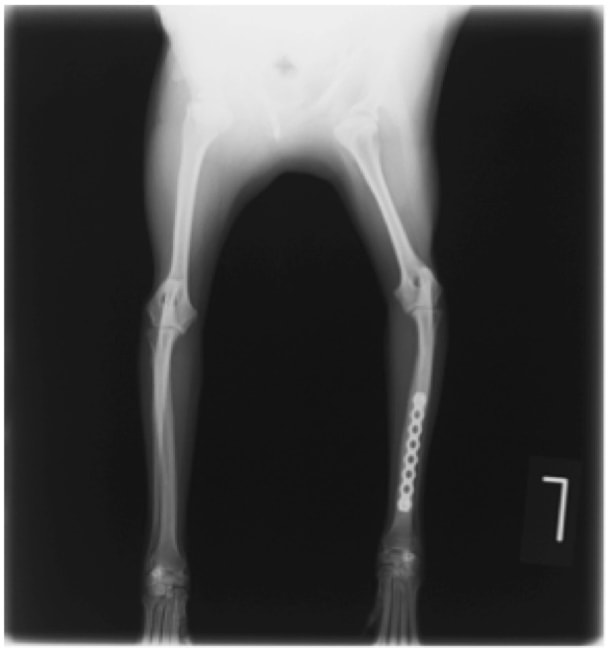

症例:交通事故による椎体脱臼

柴犬:9歳、避妊雌

交通事故直後、胸腰部に激しい疼痛、両後肢に完全麻痺を認め、シェフシェリントン徴候を呈していました。レントゲン検査において、第11-12胸椎間の脱臼が認められました。

脊髄の減圧、脊柱管の再構築・安定化を目的に、片側椎弓切除術およびMatrixMANDIBLE Plateによる椎体固定を実施しました。

隣接椎体を架橋するようにプレートを設置しました。

術後レントゲン写真